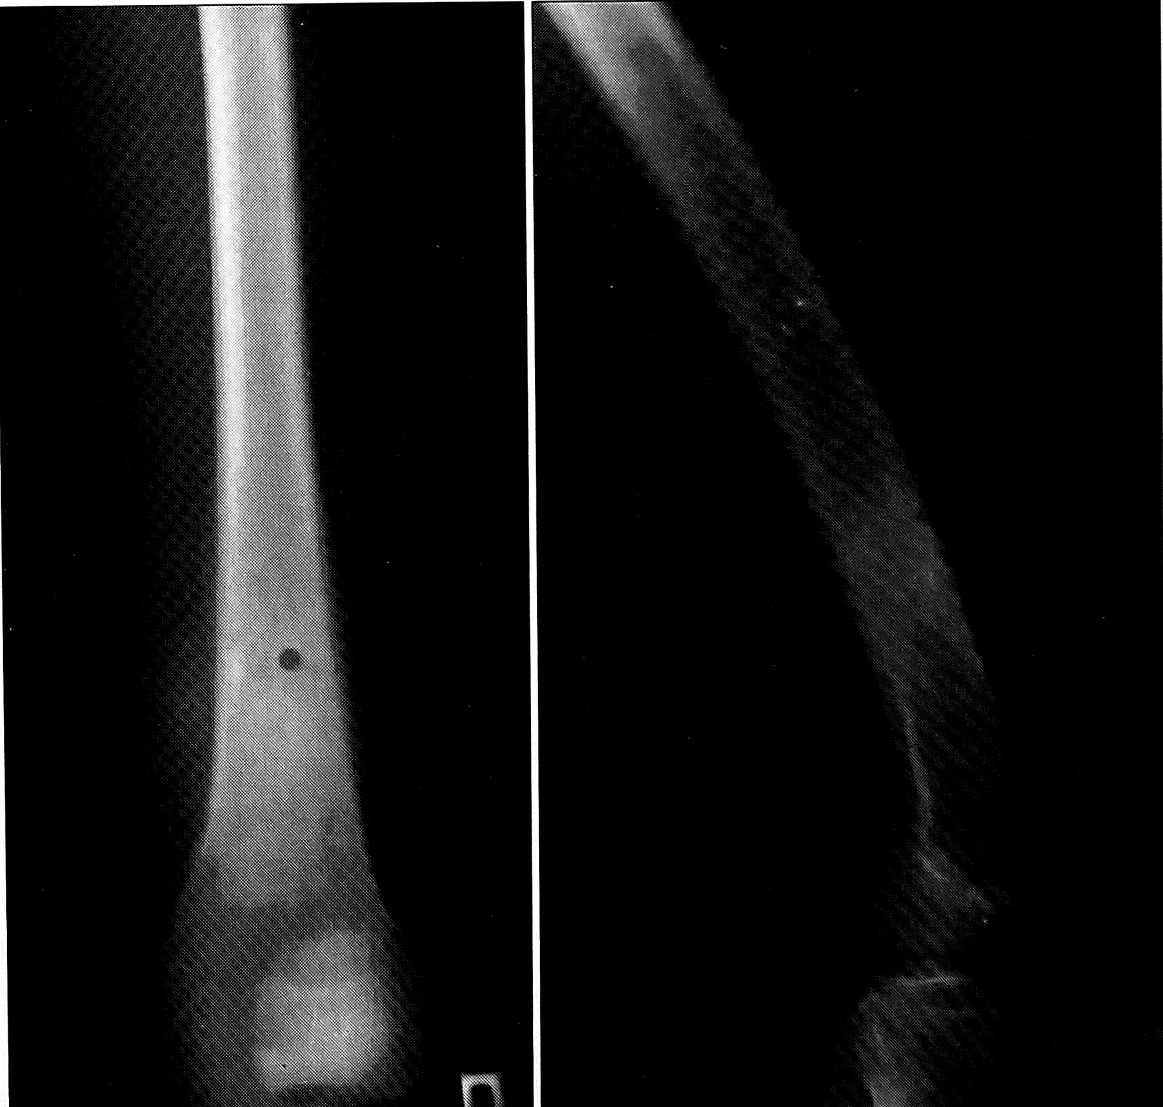

Рентгенологически в нижней трети диафиза и метадиафизе правой бедренной кости на протяжении 12,5 см определяются периостальные наслоения — бахромчатые, слоистые и спикулообразные, циркулярно охватывающие бедренную кость, но более выраженные по передней и внутренней поверхности. Контур коркового слоя нечеткий (см. рисунок). Рентгенологически изменения расценены как более характерны для периостальной остеогенной саркомы или саркомы Юинга [1, 2].

Рентгенограммы бедра больного М., 17 лет. Диагноз: метастаз рака желудка.

Клинические особенности течения болезни не противоречат характеристике опухоли как эмбрионального рака (первичное обращение пациента было связано с метастатическим поражением). Рентгенологические особенности метастатической опухоли бедренной кости, которая выглядела как остеогенная саркома или опухоль Юинга, по нашему мнению, также можно трактовать как свидетельство в пользу крайне незрелого характера злокачественного новообразования.